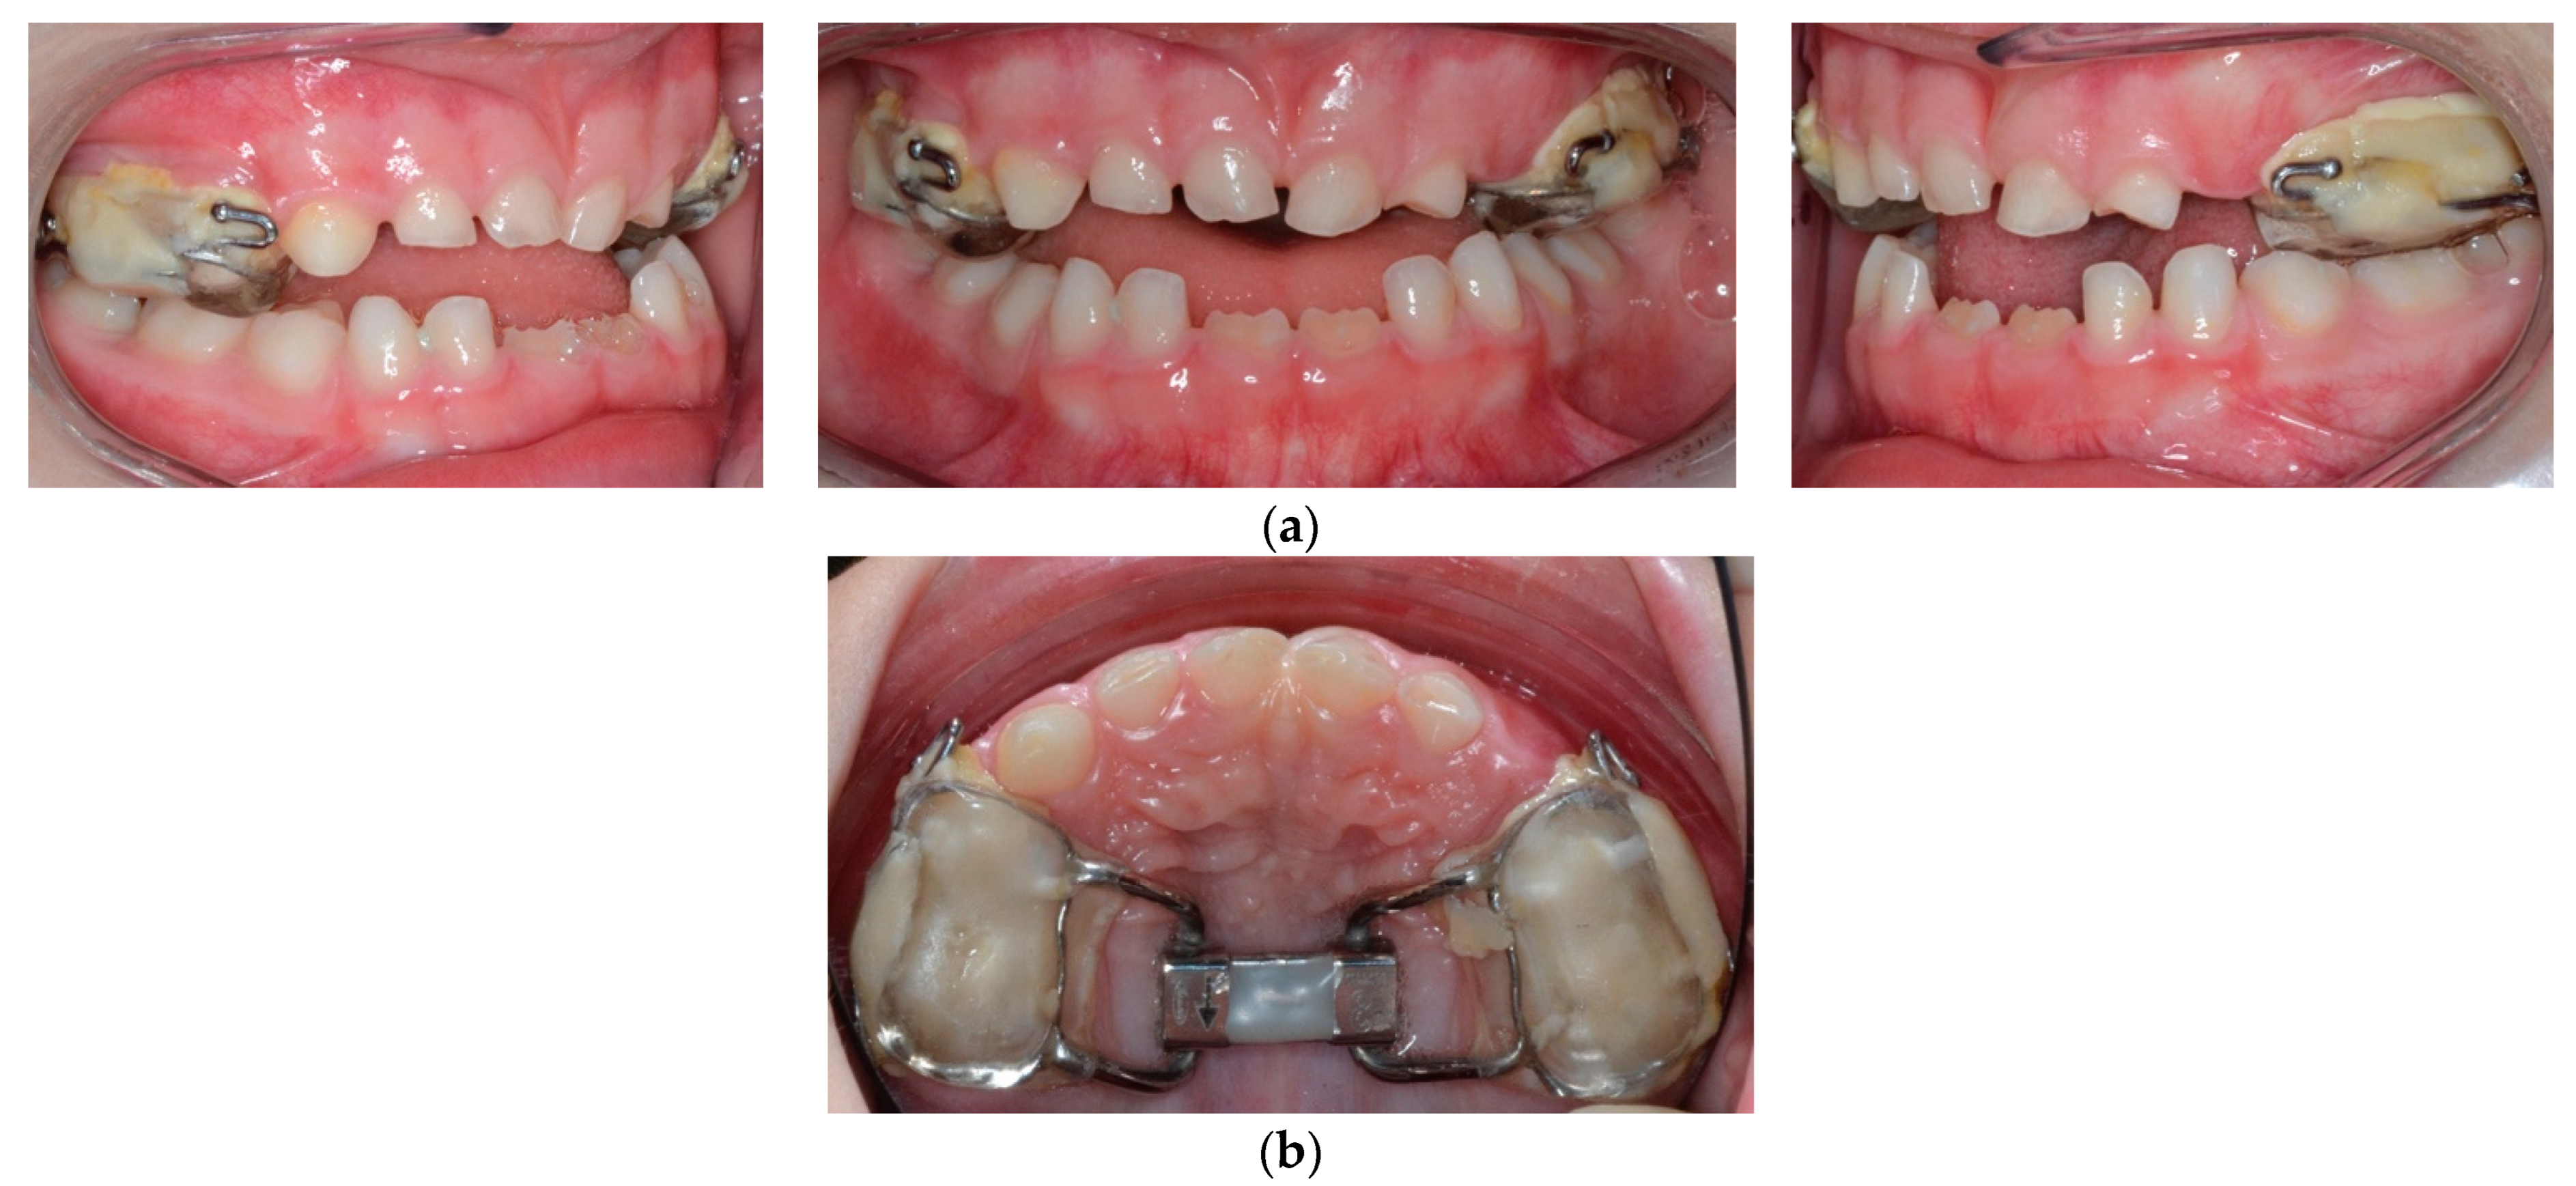

2. Case Report

4. Treatment Progress